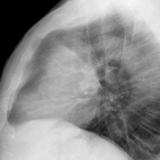

Case 9 Thymoma Lat

Date: 04/04/2010

Views: 3172